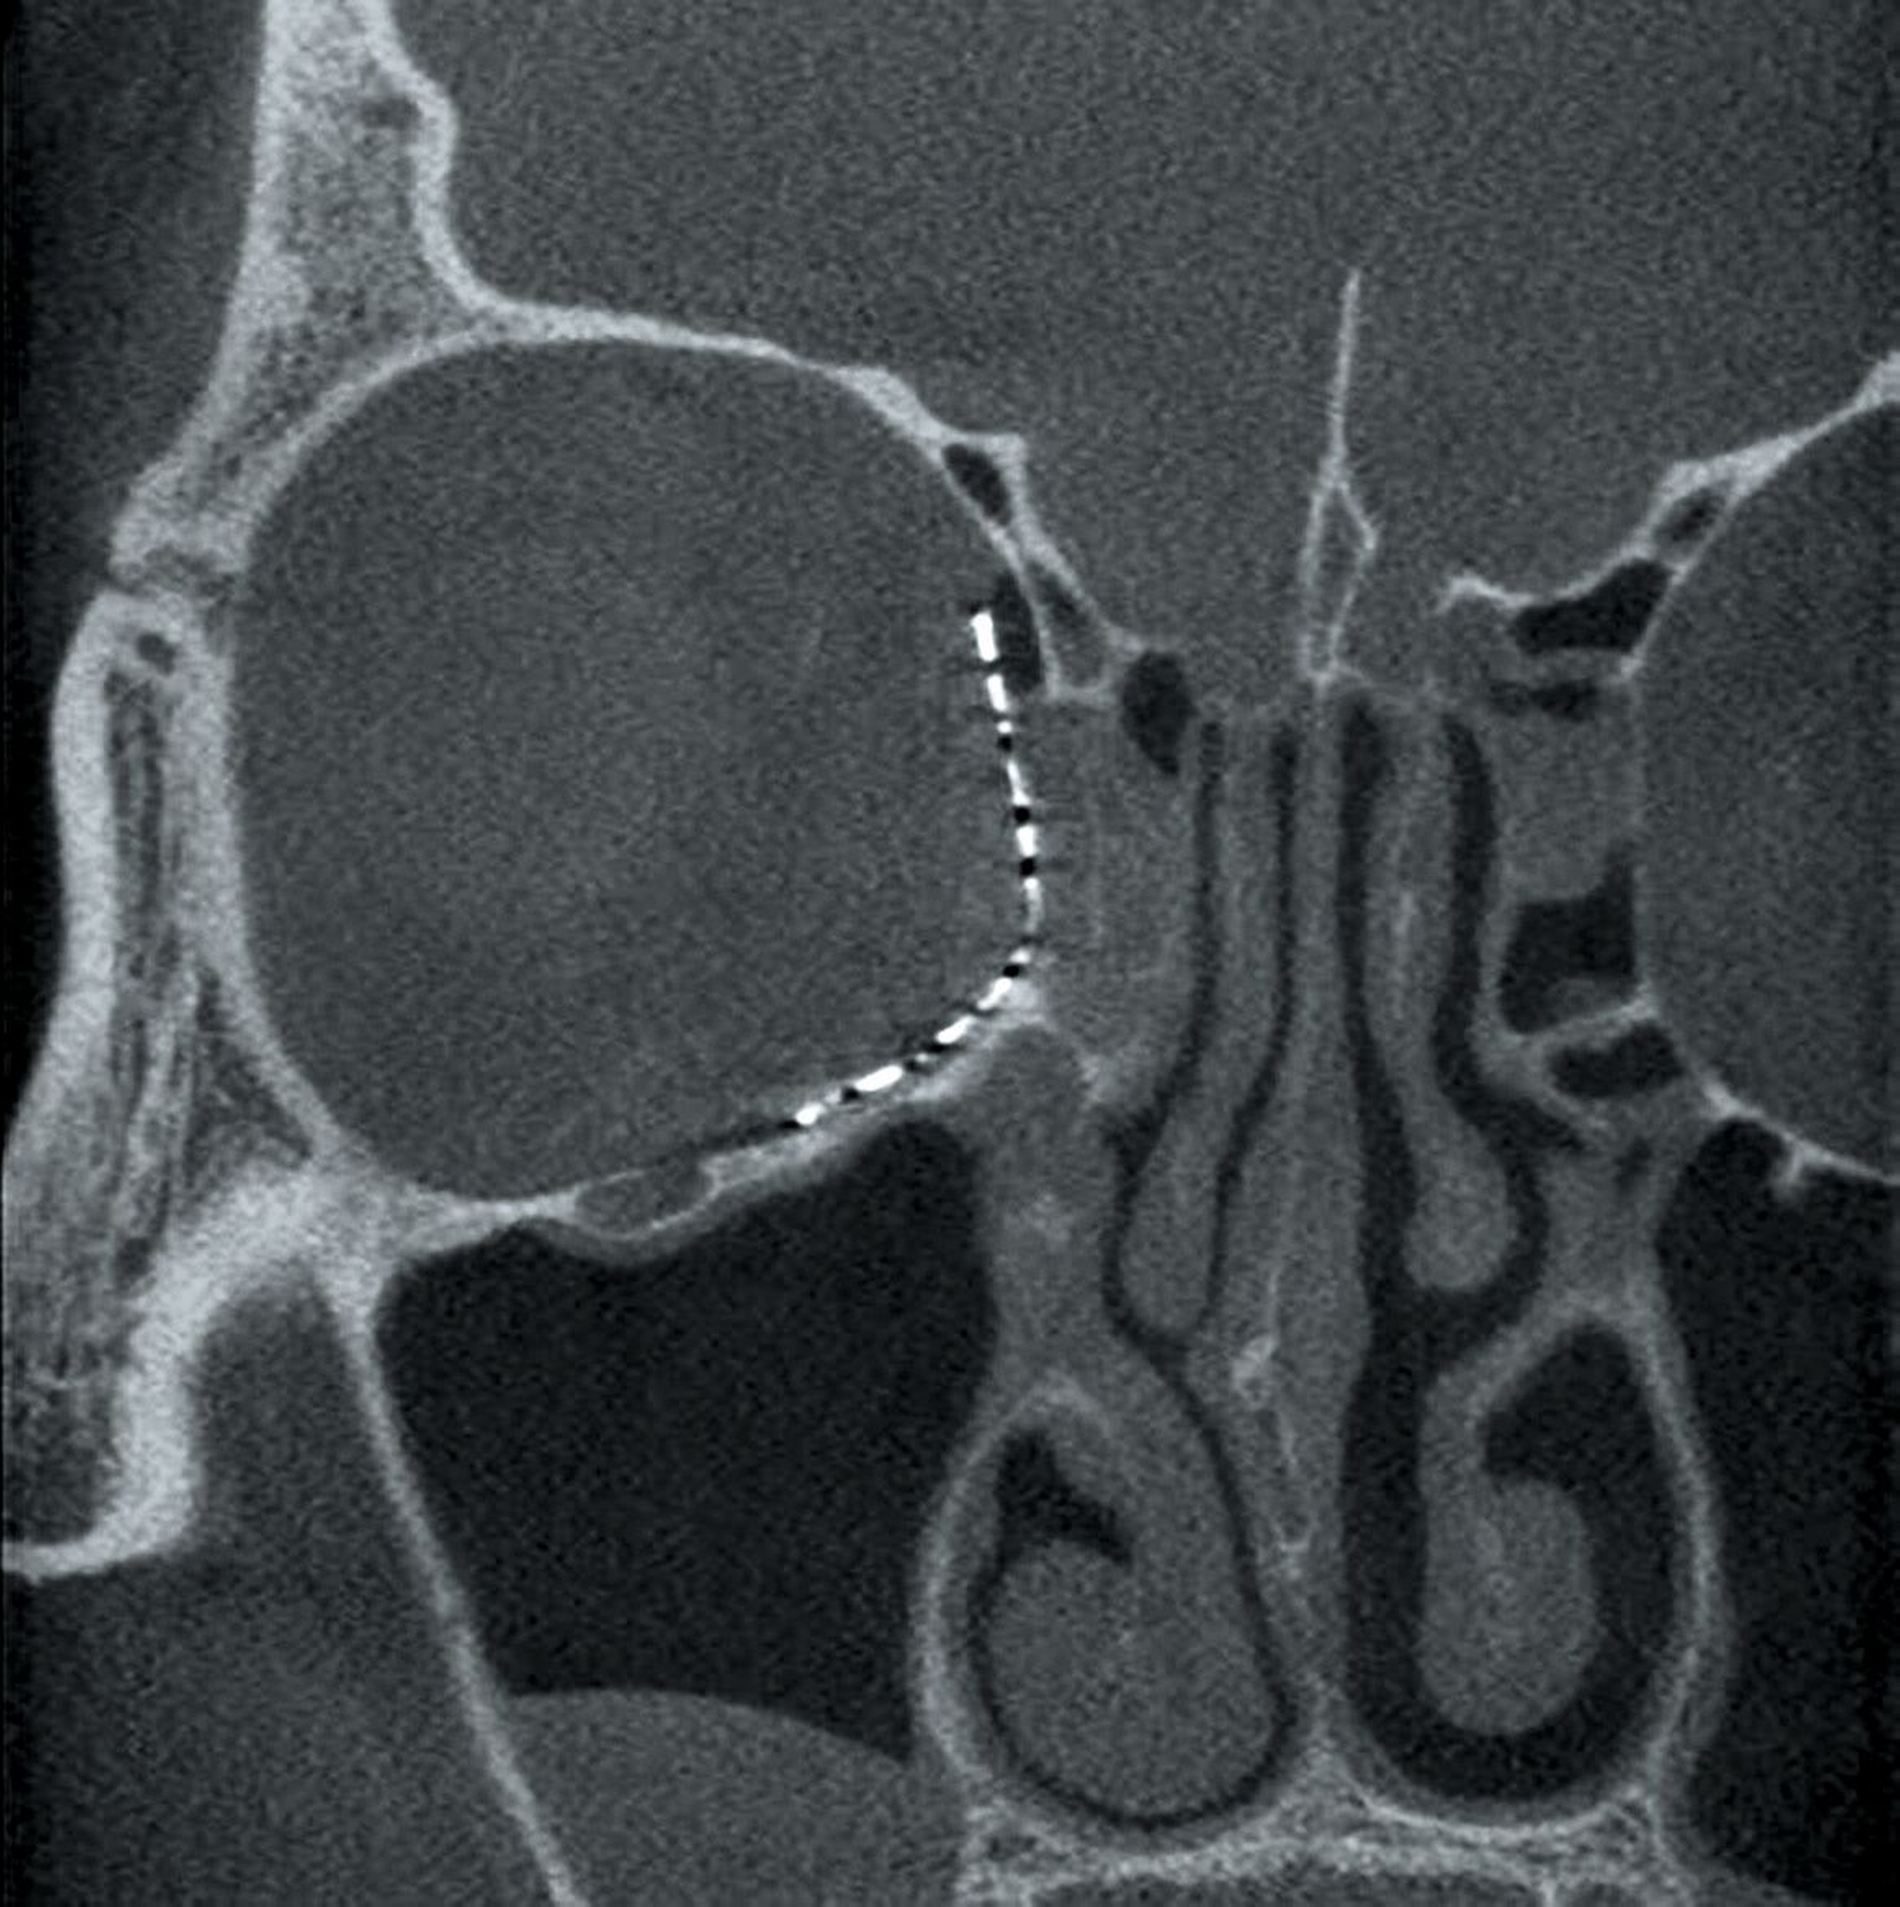

Danach wurde das angefertigte Orbitamesh in Intubationsnarkose über einen transkonjunktivalen-transkarunkulären Zugang zur Rekonstruktion der medialen Orbitawand nach Reposition des in den Defekt dislozierten Weichgewebes eingesetzt (Abbildung 3) und am Infraorbitalrand mit drei Osteosyntheseschrauben fixiert. Die postoperative Bildgebung mittels DVT zur Lagekontrolle zeigte eine korrekte Position des Implantats – entsprechend der präoperativen Planung (Abbildung 4).